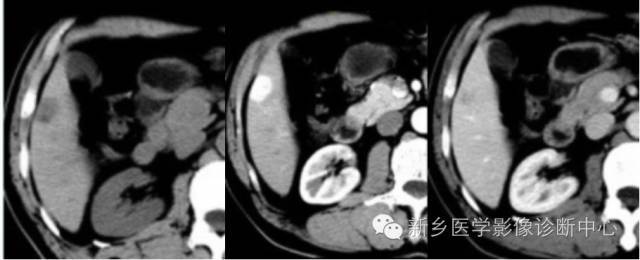

CT表现

1.平扫:肿瘤一般呈低密度,少数呈等密度。

2.动脉期:肝癌血供丰富,动脉期肿瘤明显强化,小肝癌常为均一增强浓染,大肝癌由于内部形成分隔,有不同的血管结构,而成不均匀增强效果,其差别较大。

3.门脉期:呈低密度或等密度。

4.延时扫描为低密度。